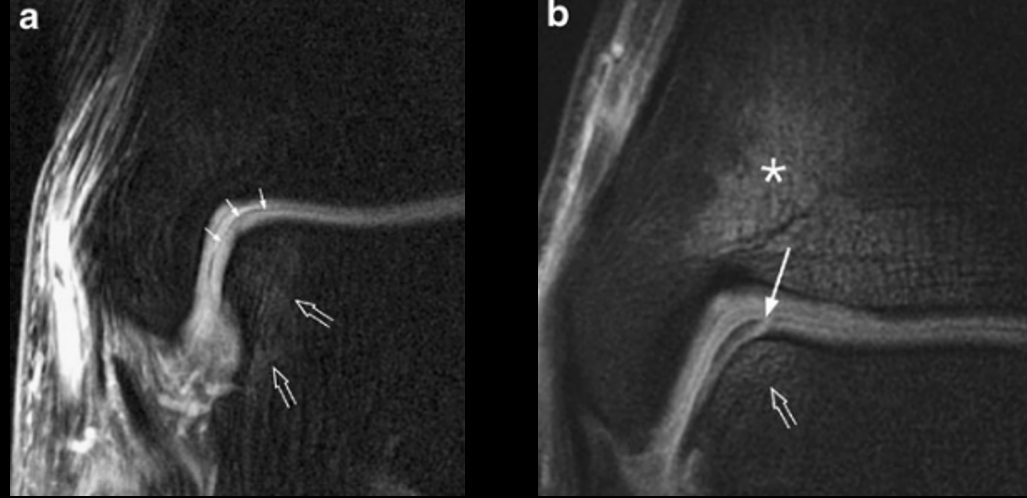

Рис. 4. МРТ: стадии 1а и 1б — повреждение хряща без (1а) и с (1б) вовлечением субхондральной кости

Рис. 5. МРТ: стадии 2а и 2б — субхондральный перелом с отёком костного мозга (2а) и без отёка (2б, хроническое повреждение)